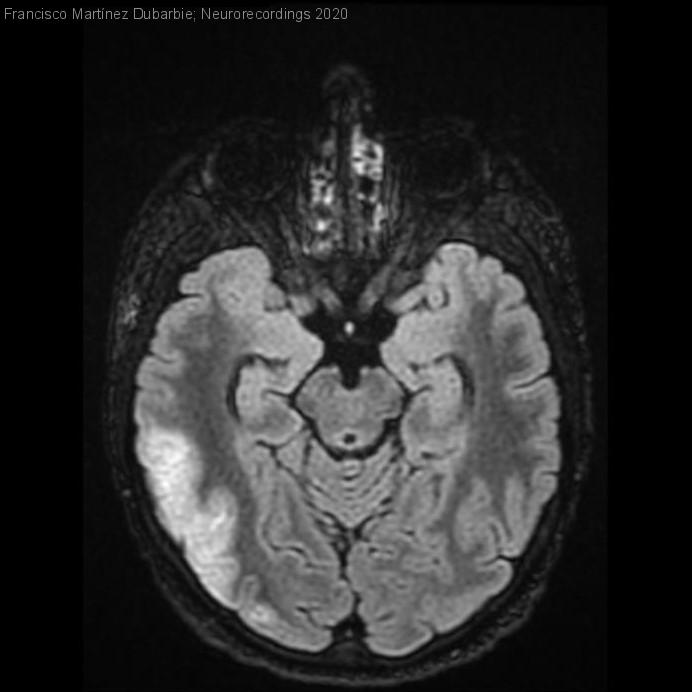

Necrosis laminar cortical en paciente joven con trasplante pulmonar

Diagnóstico final: Necrosis laminar cortical secundaria a bajo gasto cardiaco

Neurología: Epilepsia | Patología cerebrovascular

Etiología: Metabólico | Autoinmune / sistémico